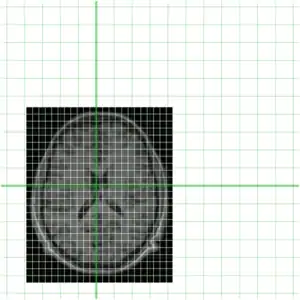

In order to get a better understanding of how mni_autoreg or indeed linear registration works, here is a simple example. Suppose we have an image of an individual and wish to align this with a model. These two images are shown below, the individuals image on the left (indiv.mnc) and model (model.mnc) on the right. Note that both of these files have different sampling and voxel sizes as illustrated by the white lines

Of course being a MINC file, both of these files represent a sampling of a world space (as defined by starts, steps and direction cosines -- use mincinfo to see this). In order to get an understanding of this, our two files are shown again below with their relative position in world space shown in green.